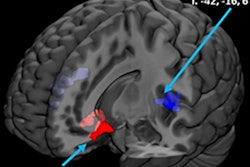

"We observed that higher gray-matter volume in bilateral caudate nucleus and in left cerebellum at age 14 years was associated with a stronger increase in alcohol use scores," wrote the researchers, led by Simone Kühn, PhD, professor of neural plasticity at the University Medical Center Hamburg-Eppendorf in Germany. "This finding fits well to previous studies pointing at an association between increases in striatum and psychiatric disease."

The MR images showed that teens with more gray matter in the caudate nucleus, which is associated with learning, and the left cerebellum, which handles thinking and movement, were more likely to increase their drinking habits over time.

Similar brain differences have been found in adolescents who progress to psychiatric disorders later in life. Debate still remains about how and why this happens. One school of thought is that gray matter expands through childhood and then peaks during adolescence, when unnecessary brain connections are "pruned away."